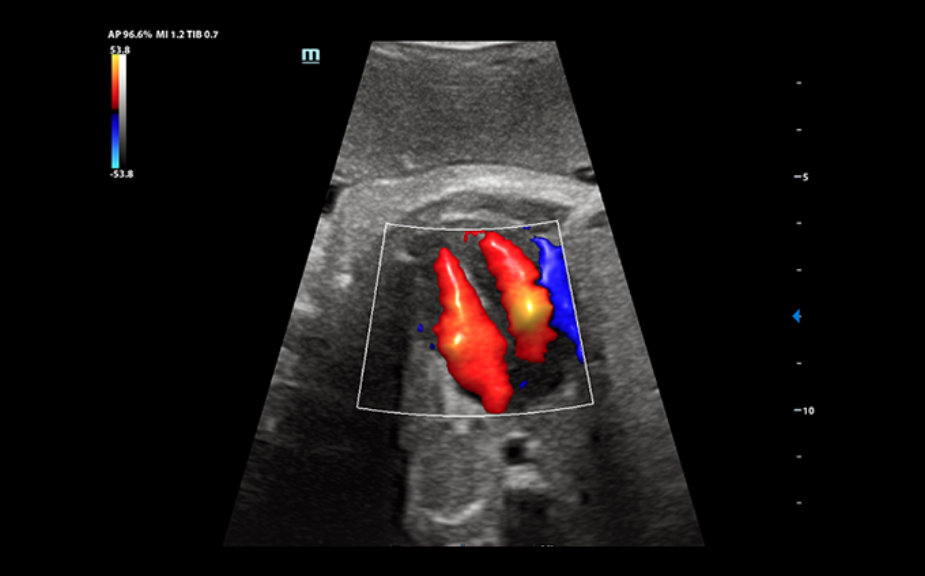

DC-80A con X-Insight mette a disposizione strumenti di una intelligenza eccezionale specifici per la cura della donna, dalla fertilit├Ā allo screening prenatale, e al post partum.

Immagini cliniche